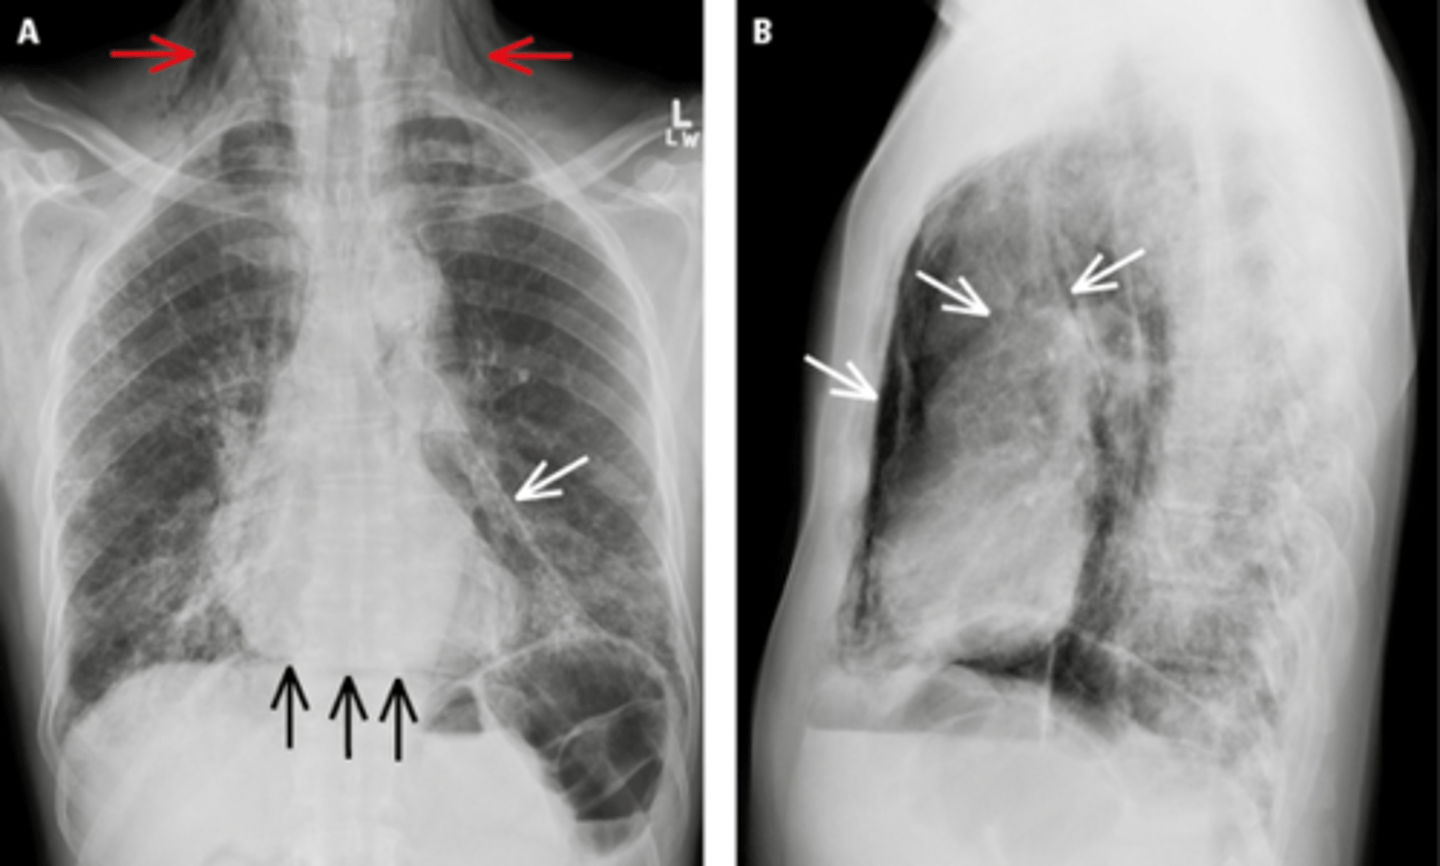

Pneumomediastinum (mediastinal emphysema)

Pneumomediastinum

Diaphragmatic rupture

Diaphragmatic rupture